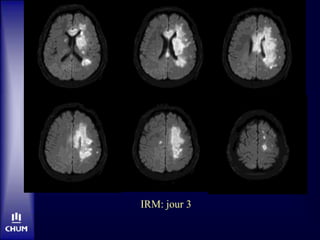

M. N.

Jour 3

• Plus somnolent, mutique

• Parésie jambe gauche

Angio-IRM: jour 3

IRM: jour 3